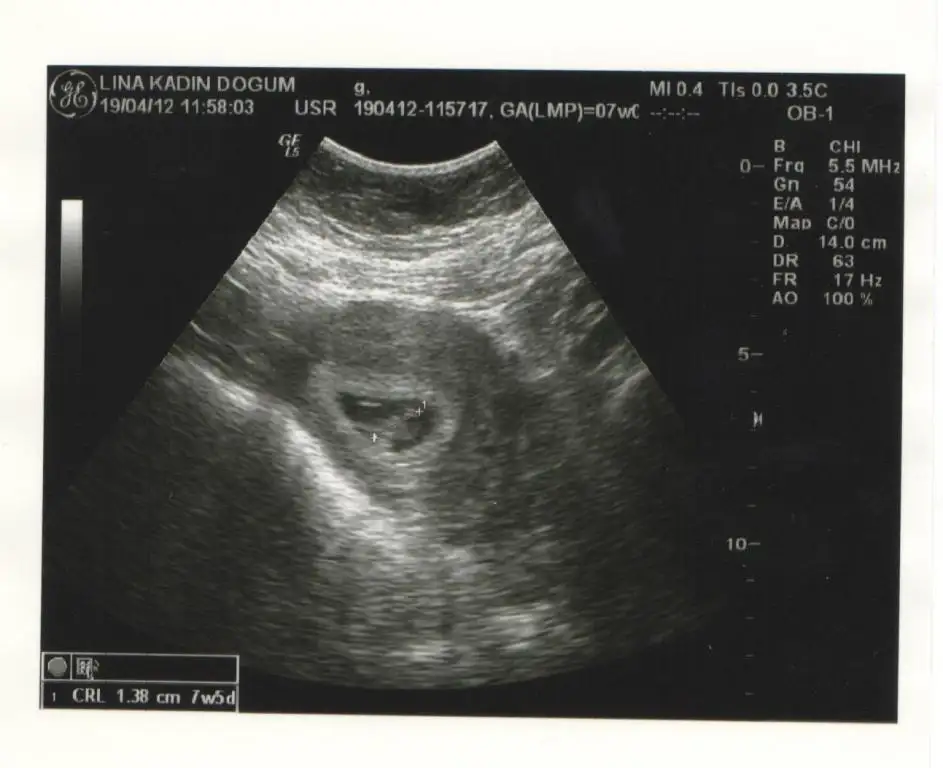

Canım bu gidişimde 7+5 haftalık ölçüldü bebek.Benim kesin bi SAT'ım yok.Ölçüme göre internette hesaplayınca tahmini doğum 30 Kasım gözüküyor.Benim 2. doğum olacağı ve sezeryan olacağı için 15gün önce alırlarmış yani tahminen Kasım ortası yada sonuna doğru denk gelecek.